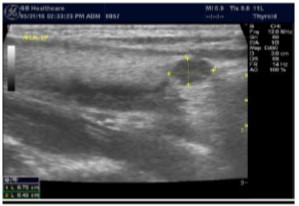

In our study many patients were found to have nodules look very much like PT adenoma, Figure 7 below. At least, 4 patients were subsequently confirmed to have parathyroid adenomas, Figure 8 and 2 patients underwent surgery

Figure 7.Thyroid nodule suspicious for Parathyroid adenoma due to its location

Figure 8.Nodule that proven to be a parathyroid adenoma, volume =5265 mm3

There are 4 parathyroid glands (2 superior, 2 inferior) imbedded within the thyroid gland. The parathyroid glands are bean-like shape and small (20-40 mg) 25. Sonographically, the parathyroid glands have the following features 25:

Hyperplastic glands: hypoechoic, volume <500 mm3.

Nodular glands: hypoechoic. Volume >500 mm3

Histologically, if the excised gland has volume <500 mm3 it is said to be hyperplastic and if the volume is more than 500 mm3 it is nodular hyperplasia in 80% of cases26. In secondary HPT, the increase in the volume of parathyroid glands is associated with increase in vascularity, as evident in Color Doppler imaging 27.